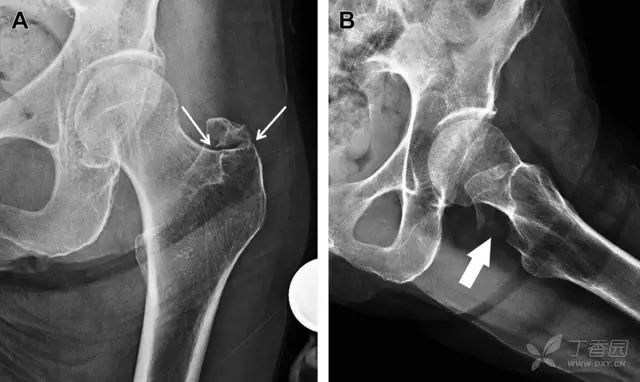

因骨结构重叠影响,股骨转子骨折发生轻度移位时亦很难发现,加做一个不同角度的 X 线片有助于诊断(图 7)。

图 7 摔倒后股骨大转子骨折。A 正位片初步检查未发现明显骨折,进一步检查发现大转子上方皮质中断(箭头)。B 蛙式侧位片示骨折分离,尤其是后方(箭头)。初步检查时忽视了这一点,是因为股骨颈未能充分显示

股骨颈应力性骨折在参加耐力运动的运动员中常见,且常发生在股骨颈压力侧。股骨颈基底部发现一垂直于骨皮质的线性硬化带可诊断这种类型的疲劳性骨折(图 8)。

图 8 长跑运动员股骨颈应力性骨折。X 片(A)和冠状位 CT 多维重建(B)图像示穿过股骨颈内侧皮质中的透亮区(箭头),周围硬化。骨折垂直于皮质

股骨颈张力侧的应力性骨折有可能发展为完全骨折(图 9)。

图 9 进食障碍患者股骨颈应力性骨折的张力侧。A 正位片示股骨颈完全骨折。B 2 周前的 X 片示局部骨量减少,正是后来发生骨折的位置(箭头)